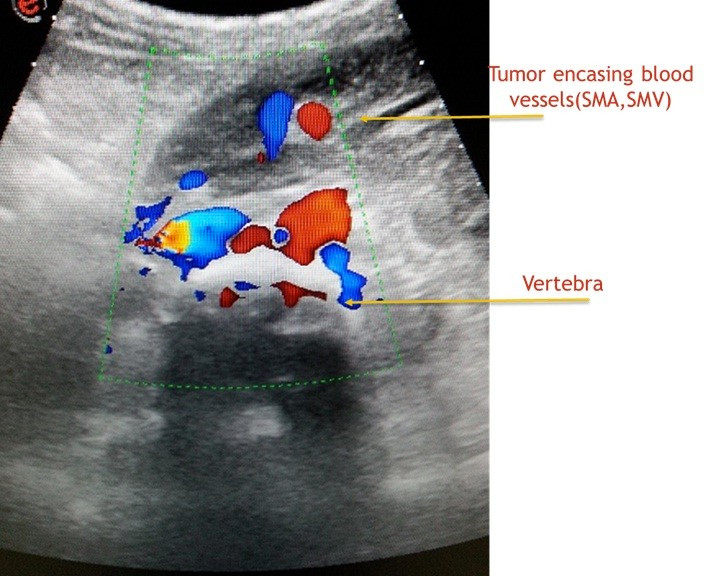

Till i spoke to him ,i thought he had a common easily curable illness.I learnt from him that ,in last 3 months he consulted 2 doctors,one of them a surgeon with no respite.One had treated him empirically and while  the other had referred him to a vascular surgeon,specialist dealing with blood vessels of legs .The vascular surgeon rightly requested a blood vessel study(Doppler ultrasound test)of the leg.I did a detailed examination of veins and arteries of the leg and found them normal.And  radiologists do not stop till they unearth the mystery of diagnosis.I gently interrogated his abdomen with ultrasound.I was not happy with what i found.It was a  dangerous tumour (sarcoma )involving muscles and deep structures of abdomen(retro peritoneum)impeding the fluid flow from leg and hence causing its swelling. Had the radiology scan been performed earlier,delay in diagnosis could have been avoided.

One cannot neglect leg swelling irrespective of the age.Appropriate diagnostic scanning should be carried out in consultation with radiologist.